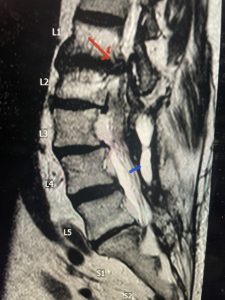

(Figs 5a): Sagittal (a) and axial (b) T2-weighted lumbar MRI demonstrating status post lumbar decompression and insitu fusion L2-5 now well decompressed (blue dash) with development of new (red arrow) severe stenosis and with superimposed right L1-2 disc herniation (blue arrow)

(Figs 5b)